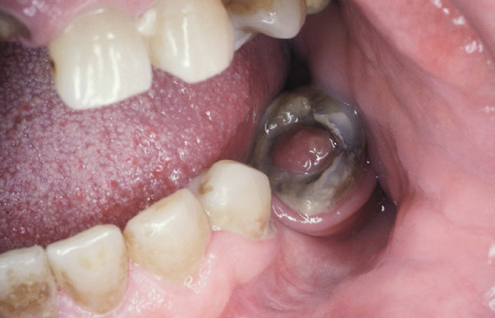

What is this condition?

Chronic hyperplastic pulpitis

What is chronic hyperplastic pulpitis?

Pulp that is coming up out of the tooth.